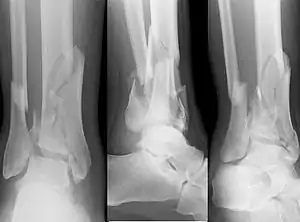

![]() | |

| X-ray of a fracture involving the articular surface of the Tibia | |